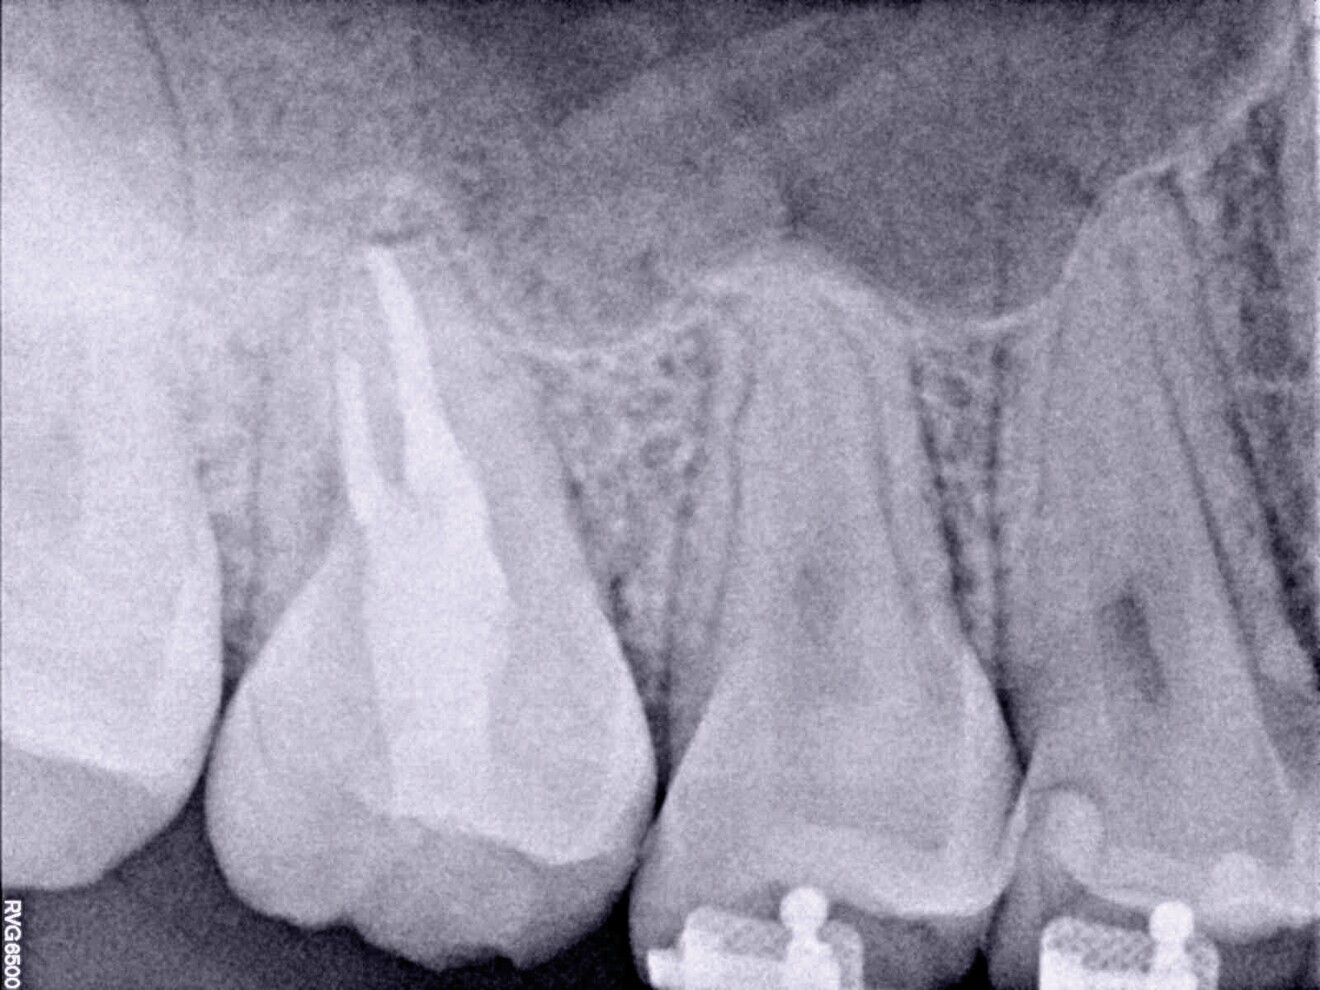

La patiente s’est présentée au cabinet huit mois plus tard avec des signes et des symptômes de nécrose pulpaire et d’abcès périapical aigu mis en évidence par une radioclarté. La zone rétromolaire était bien cicatrisée (Fig. 6). Dans des cas comme celui-ci, où la structure coronaire est encore intacte, il est conseillé de recourir aux nouvelles techniques endodontiques et d’adopter une approche conservatrice du traitement endocanalaire afin d’obtenir de meilleurs résultats. Le puits d’accès endodontique a été créé au moyen de fraises à haute vitesse et d’inserts ultrasoniques. Le protocole de nettoyage et de mise en forme a été réalisé à l’aide de canules et de limes flexibles en alliage à mémoire de forme contrôlée (Aurum Blue, Meta Biomed), dont les propriétés sont particulièrement importantes lors de la pénétration dans les canaux radiculaires par l’accès conservateur (Figs. 7a et b).

Les limes endodontiques dont l’alliage est stabilisé en phase martensitique (mémoire de forme contrôlée) sont en effet dotées d’une meilleure résistance à la fatigue cyclique.11, 13, 14 Les canaux radiculaires ont été obturés au moyen d’un ciment de scellement endodontique à base de silicate de calcium activé par ultrasons (CeraSeal et EQ-S, Meta Biomed) et de gutta-percha (Figs. 8a–c). Cette étape du traitement peut s’avérer délicate en présence d’un accès endodontique de très petite taille.

L’utilisation d’un ciment de scellement endodontique à base de silicate de calcium facilite le processus d’obturation, et l’activation ultrasonique permet de distribuer le matériau sur toute la longueur du système des canaux radiculaires nettoyés et mis en forme (Fig. 9). Une restauration coronaire adhésive a été effectuée dans le cadre de la même visite au moyen d’un matériau de reconstitution corono-radiculaire à double polymérisation (NexCore, Meta Biomed) pour la cavité pulpaire et d’un composite compactable pour la surface occlusale (Ezfi l, Meta Biomed ; Figs. 10a et b). La dent était fonctionnelle et asymptomatique, et la patiente a dès lors pu commencer son traitement orthodontique. La radiographie prise à l’occasion du suivi à trois ans a montré un tissu périapical sain (Fig. 11).